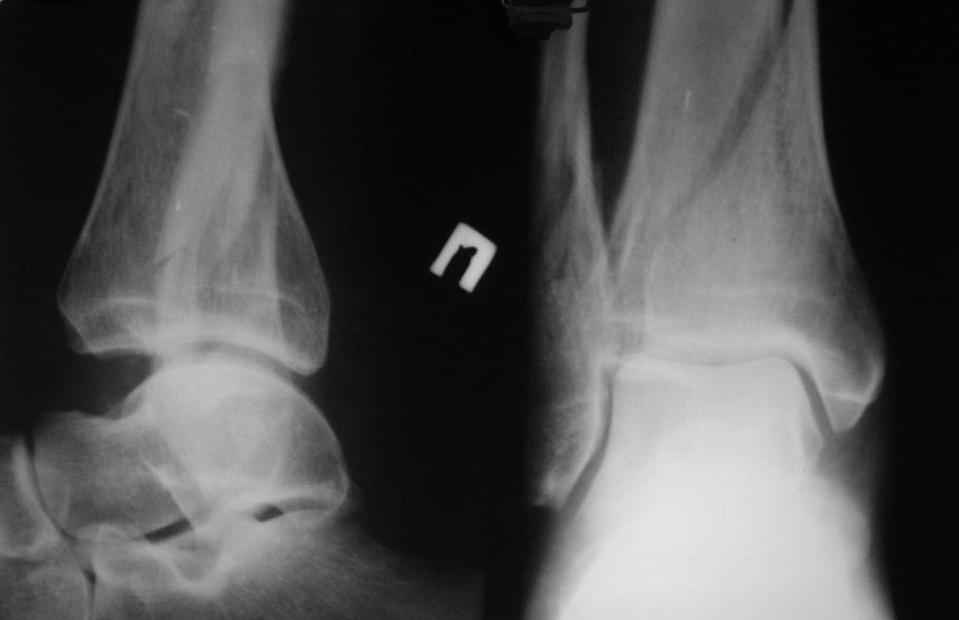

помогите определиться с тактикой лечения даного перелома пилона

Больной, 46 лет. Травма 27.08.08. При поступлении, в травмпункте была проведена блокада места перелома, иммобилизация гипсовой повязкой. Единого мнения по поводу дальнейшего лечения пока нет. Просьба высловиться по поводу возможностей лечения даного перелома, вообще возможности оперативного лечения. Спасибо за ответы.

прошу прощения за то, что забыл приложить снимки

открытая репозиция и фиксация

- малоберцовая - 3.5 мм 1\3 трубчатая пластина.

- большеберцовая - масса вариантов, начиная с множественных шурупов без пластины и заканчивая locking plate для дистальной тибии